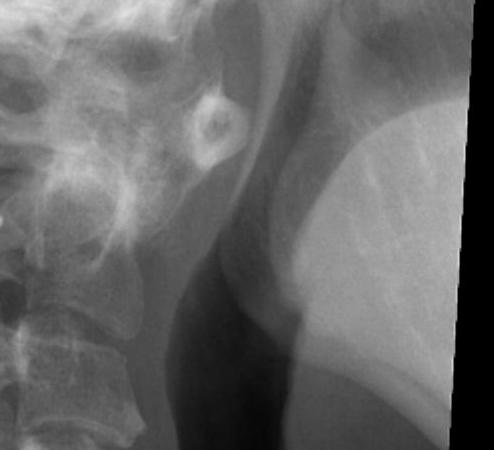

Basilar invagination / Vertical subluxation

Definition

Superior migration of the odontoid into foramen magnum

Pathology

Due to erosion of lateral masses of atlas and occipital condyles

- can lead to compression of brain stem

- risk of myelopathy / sudden death

Diagnosis

Ranawat measurement < 13 mm

- line between anterior and posterior arch C1

- centre of pedicle of C2

McCrae

- line of foramen magnum

- tip of odontoid should not protrude above this line

McGregor line > 4.5 mm

- line hard palate to posterior occiput

- if tip of dens > 4.5 mm above this line = vertical settling

- severe > 8 men or > 10 women

Redlund-Johnell measurement

- assesses entire occiput to C2 complex

- base of dens to McGregor line

- men < 34mm / women <29 mm = abnormal